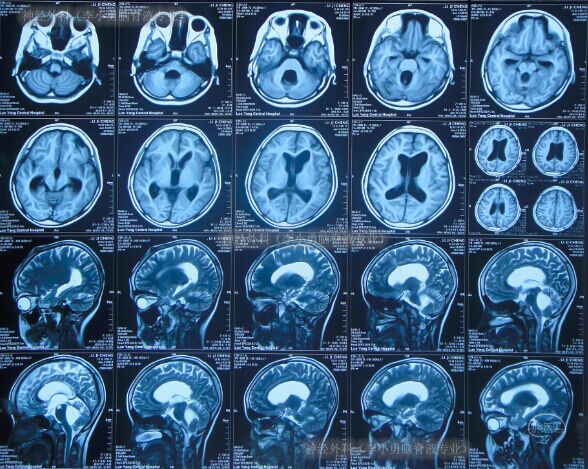

第1次分流术后第6年即2012年2月29日(10岁时),无明显诱因突然出现呕吐、腹部膨隆;急诊第2次就诊于第1家医院:河南省洛阳市某医院,查头颅CT显示脑室系统显著扩大,且第四脑室也显著扩大(图-1),脑积水复发。

图-1:2012年2月29日头颅CT

术后症状逐渐改善,至术后第5日即2012年3月19日,症状完全消失,腹部膨隆减轻;复查头颅CT示脑室系统较入院时(2012年2月29日)有所缩小(图-3)。

图-3:2012年3月19日头颅CT